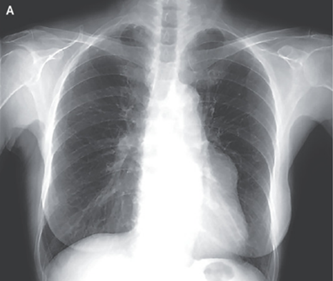

34歳男性。4~5前から続く右胸痛・咳嗽。2日前より呼吸困難感が出現。 SpO2 93(r.a) 呼吸音:右で減弱。 X-p: 右肺は高度虚脱。 縦隔の左方変位…